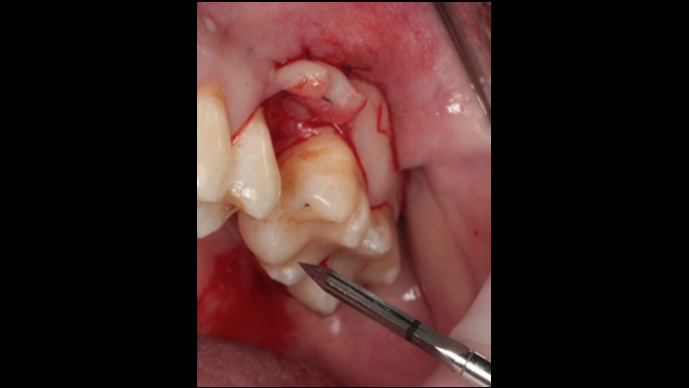

Clinical case: Ridge splitting technique using SmarThor + AnyRidge as expander

- Courtesy of Dr.Kwang-Bum Park, Korea -

AnyRidge, ridge splitting, GBR, Dr. Kwang-Bum Park, mandibular posterior, SmartThor, Mega-Oss, thin ridge, bone regeneration

Products:

AnyRidge implant system. SmarThor, Mega-Oss